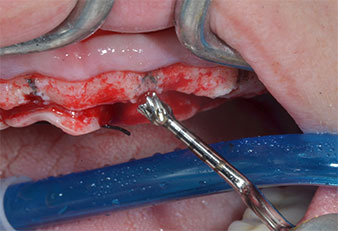

Wegen des relativ harten Knochens (D2) an den Positionen 11 und 21 wurden die 10 mm langen Implantatlager in diesem Bereich abschließend mit einem 4-mm-Spiralbohrer, dem chirurgischen Winkelstück WS-75 L von W&H und dem W&H Implantmed Implantologiemotor in Verbindung mit dem optionalen W&H Osstell ISQ module präpariert. Im Gegensatz dazu wurde der weiche Knochen der Implantatlager im Seitenzahnbereich mit dem Piezomed I3P auf den abschließenden Durchmesser von 3 mm erweitert. Die Implantate wurden dann transgingival eingesetzt, die Einheildauer betrug drei Monate (Abb. 6-10). Die vorhandene Prothese wurde auf vier provisorischen Implantaten abgestützt (Abb. 8).